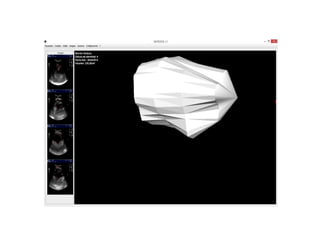

• 6.

NEFROVOL Parallel 2Dimages along main axis User to define boundaries in each 2D Build a mesh Extrapolate at the ends Count contained elements Use scale to estimate volume

• 7.